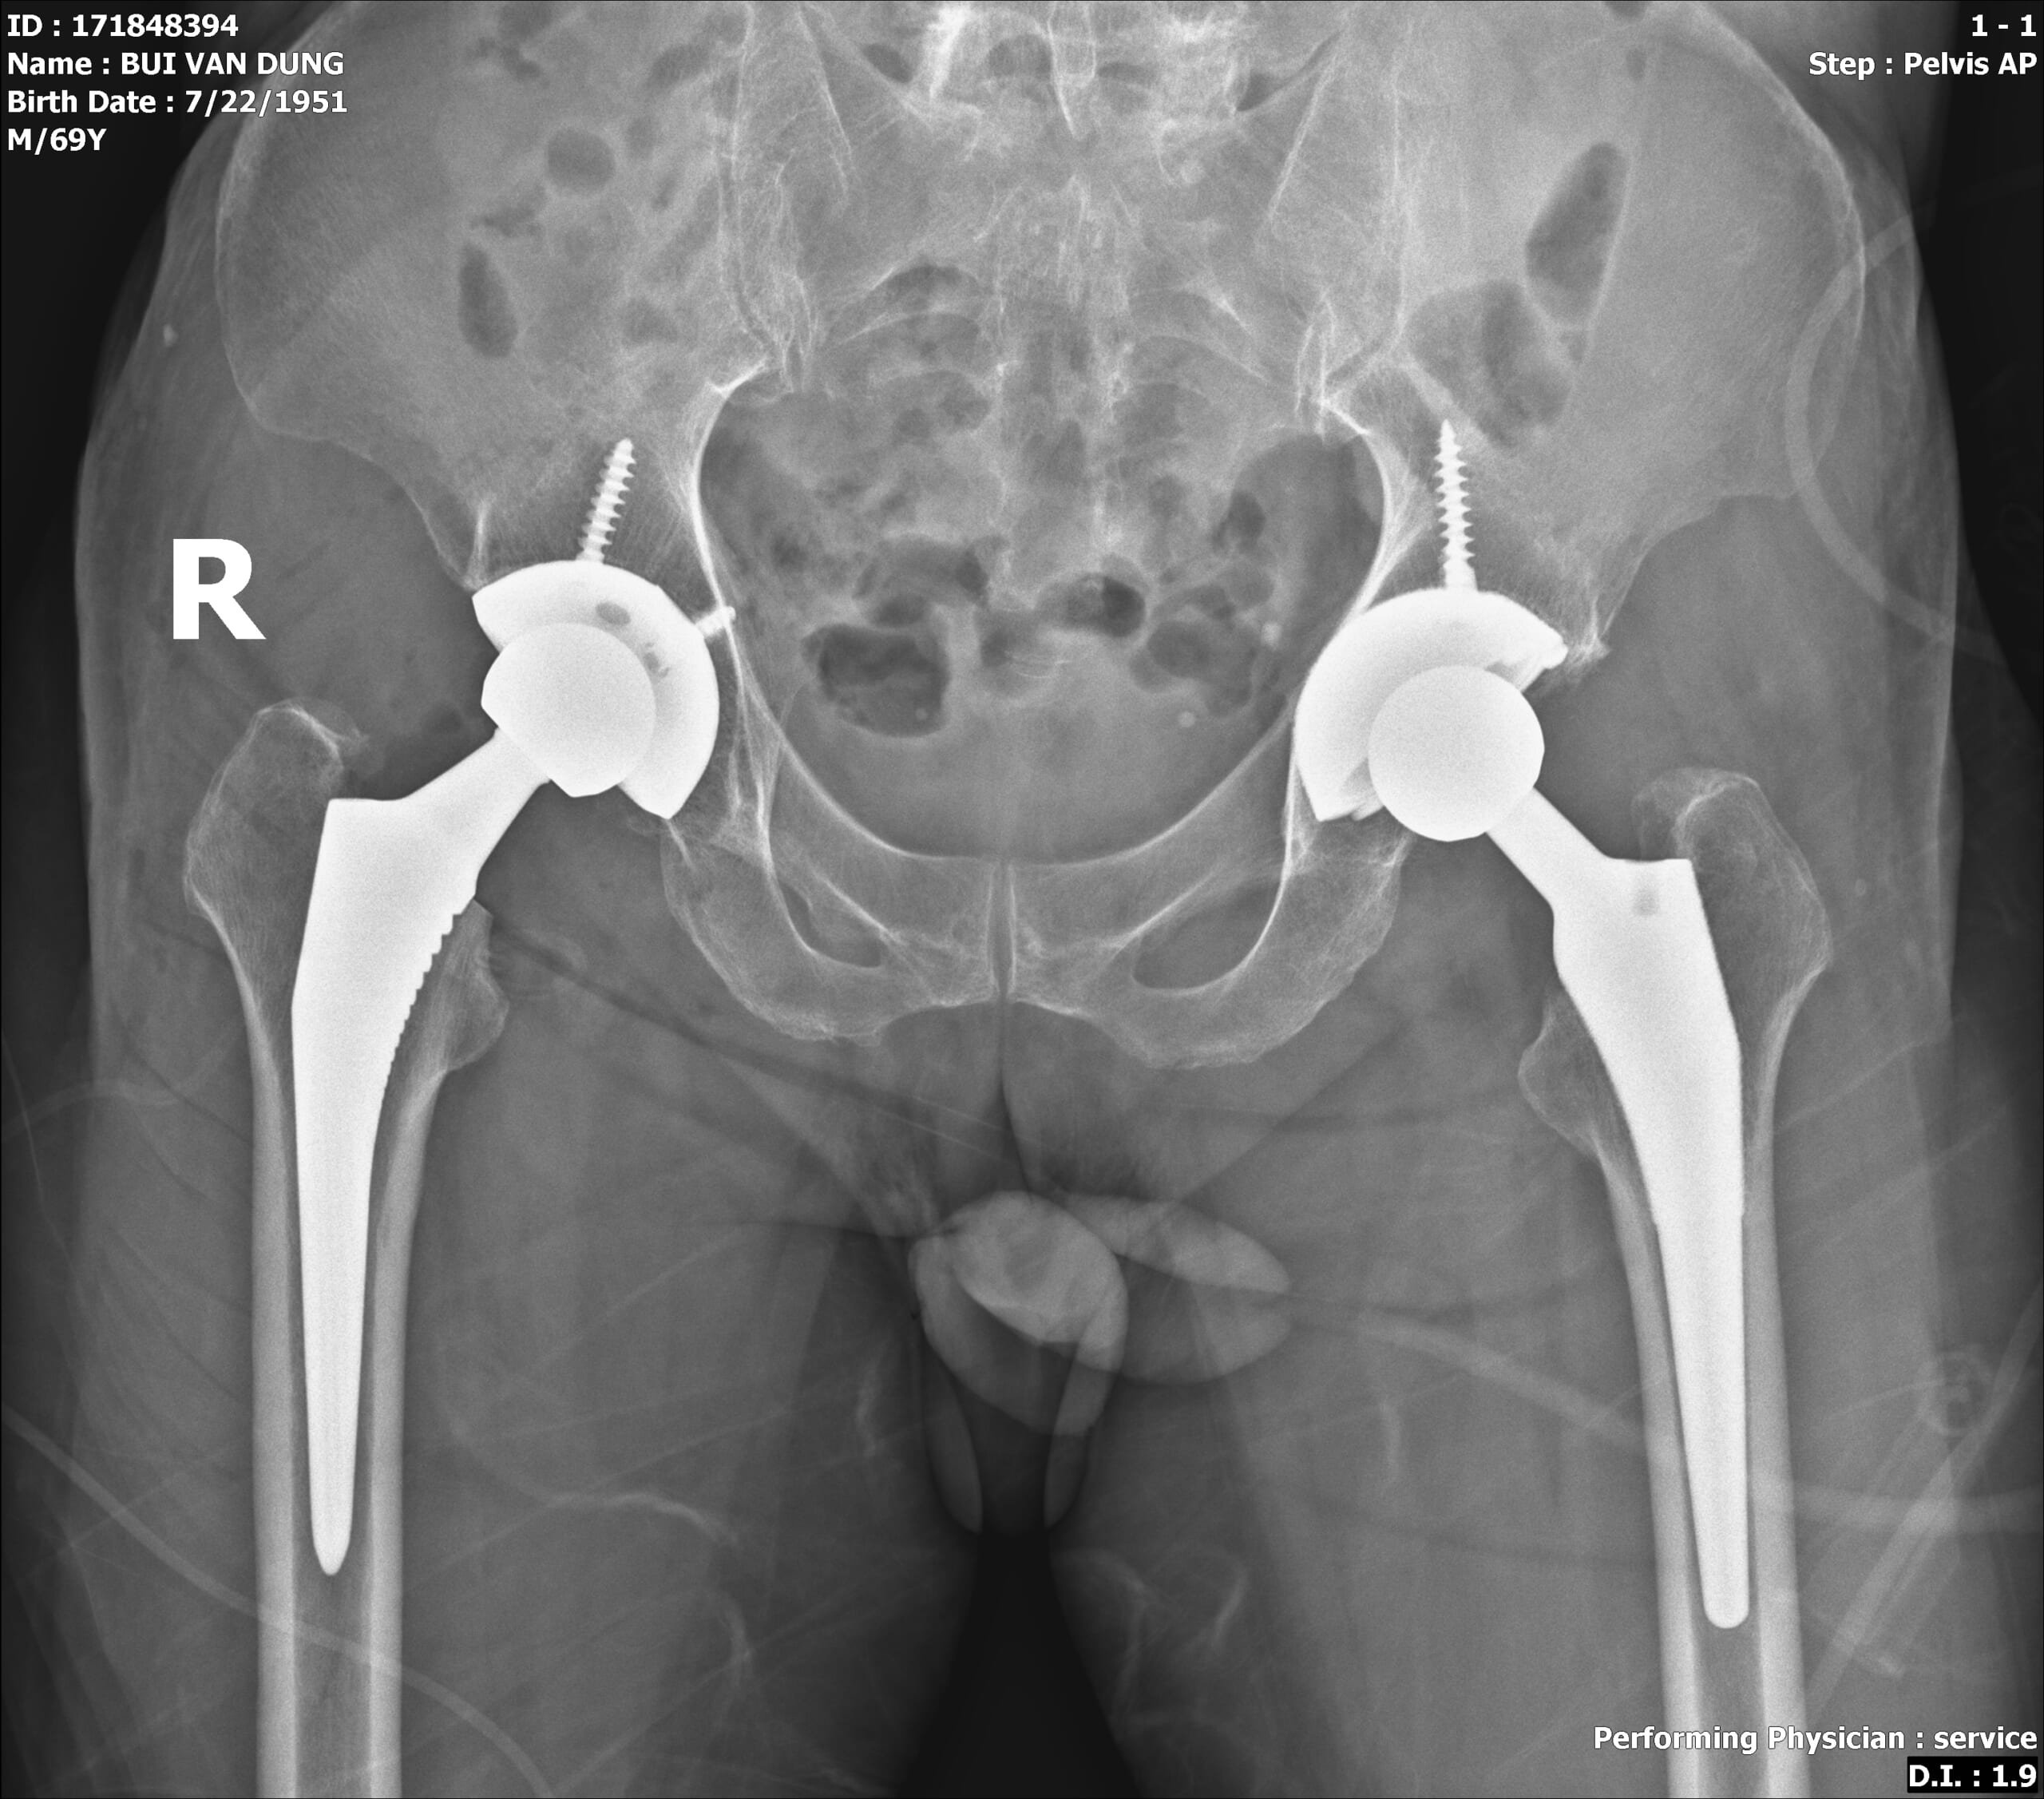

thoai-hoa-khop-hang Ảnh: Hình ảnh phim X-quang cả hai bên khớp háng bị thoái hóa đã được thay khớp háng nhân tạo của bệnh nhân Bùi Văn Dũng (70 tuổi)

Sau hai lần bệnh nhân được phẫu thuật thay khớp háng (trái và phải), hiện chân trái đã vận động bình thường, chân phải đang trong quá trình hồi phục. Bệnh nhân đã có thể đứng lên thực hiện các bài tập đi và vận động nhẹ nhàng.